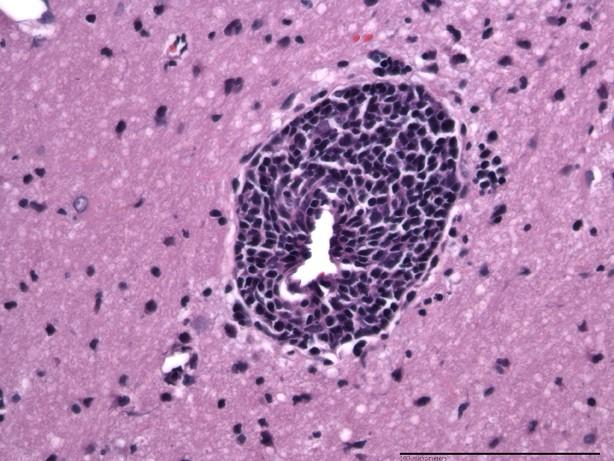

Within a group of 30 SIV-infected macaques treated with cART, researchers found that 17 of the animals developed lymphocyte-dominant inflammation around blood vessels in the brain or meninges that was clearly different from what is typically seen with severe SIV and HIV infection of the central nervous system (CNS). The high prevalence of lesions and lack of overt neurologic symptoms among these macaques support the premise that robust or dysregulated adaptive immune responses in the CNS may impact treated HIV patients at a subclinical level and may contribute to the continued high prevalence of HIV-associated neurocognitive disorders.

The researchers conducted pathologic evaluation of all major brain regions to characterize the composition of cellular infiltrates and investigated associations between the severity of CNS inflammation and SIV viral loads in the plasma, cerebrospinal fluid (CSF), and brain tissue. Because the CNS lesions found in cART-treated macaques shared some similarities to the inflammation reported in HIV patients with immune-mediated neurologic disorders, such as CNS immune reconstitution inflammatory syndrome and symptomatic CSF escape, researchers also looked for, but found no evidence of known risk factors for these conditions including opportunistic infections and severe immune suppression prior to treatment (low CD4 nadir).

Inflammation was associated with low levels of SIV RNA in the brain and was more common in animals with episodes of CSF viral rebound or sustained detectable levels of virus in the plasma and CSF during treatment.